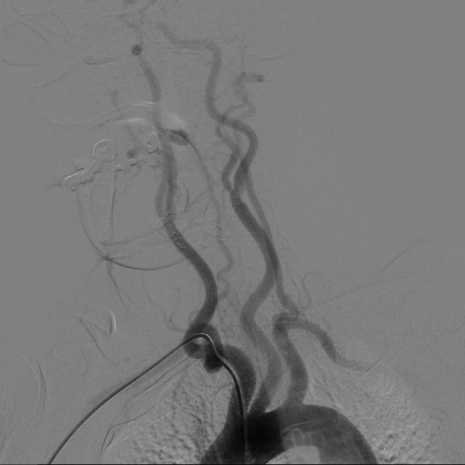

入弓:

泥鳅导丝辅助下,将Pigtail猪尾巴管送入升主动脉,行主动脉弓造影;完成造影后,放入泥鳅导丝把猪尾巴管撑直,然后将泥鳅导丝和猪尾巴管一同退出体外;也可以沿猪尾巴管放入0.35in 260cm交换导丝,保留导丝交换出猪尾巴管,再由SIM2管沿交换导丝放入主动脉弓;或此步骤用泥鳅导丝将SIM2管带入主动脉弓。

造影:

调整SIM2导管头端位置,将造影导丝放入降主动脉,SIM2管随造影导丝进入降主动脉;撤回造影导丝,顺时针或逆时针轻轻扭动SIM2导管,让其成袢;慢慢回拉成袢的SIM2导管,让其头端跳入左锁骨下动脉口,造影剂冒烟证实后,适当调整导管头端位置和张力后,行左侧锁骨下动脉造影;若有需要,可沿导管置入泥鳅导丝超选进入左侧椎动脉,行左椎动脉超选造影;旋转并内送SIM2导管让其再次成袢,缓慢回拉并适当旋转导管,让导管头端自然跳入左侧颈总动脉,必要时可适当旋转导管,帮助其寻找到左侧颈总动脉;旋转导管解袢,行左侧颈总动脉造影,或用泥鳅导丝协助超选进入左侧颈内动脉,行左侧颈内动脉超选造影;旋转并内送SIM2导管让其再次成袢,缓慢回拉并适当旋转导管,让导管头端自然跳入无名动脉;导管进入无名动脉后,边回拉边冒烟,让导管头端对准右侧颈总动脉并顺利进入,解开导管袢,必要时用泥鳅导丝助其超选进入右侧颈内动脉,完成右侧颈内动脉造影;回拉导管至右侧锁骨下动脉,冒烟证实在右侧椎动脉口附近时,行右侧锁骨下动脉造影;路途下,用泥鳅导丝把SIM2管带入右侧椎动脉,行右侧椎动脉超选造影。

旋转导管成袢后,冒烟下轻推/拉导管找血管口,挂上血管后做路标

SIM2导管过弓要点

右侧为升主动脉,左侧为降主动脉;升主动脉部成袢易损伤主动脉瓣,可能致心律失常,慎用;通常 在降主动脉成袢;导丝进入降主动脉后,再部分推入SIM2导管,撤导丝,轻轻退并 顺时针旋转导管,成袢;对于3型弓,导丝过弓可能困难,建议导丝塑大弯,路图下过弓。

左椎动脉超选

部分患者因为弓型问题及左 侧椎动脉开口高低问题, SIM2不一定能顺利进入左侧椎动脉。

解决办法:

通过旋转导管,使导管后 退或头端指向椎动脉开口再 入导丝,一定要稳且慢,导 管的跳动可能导致夹层;用SIM1或SIM3导管尝试。